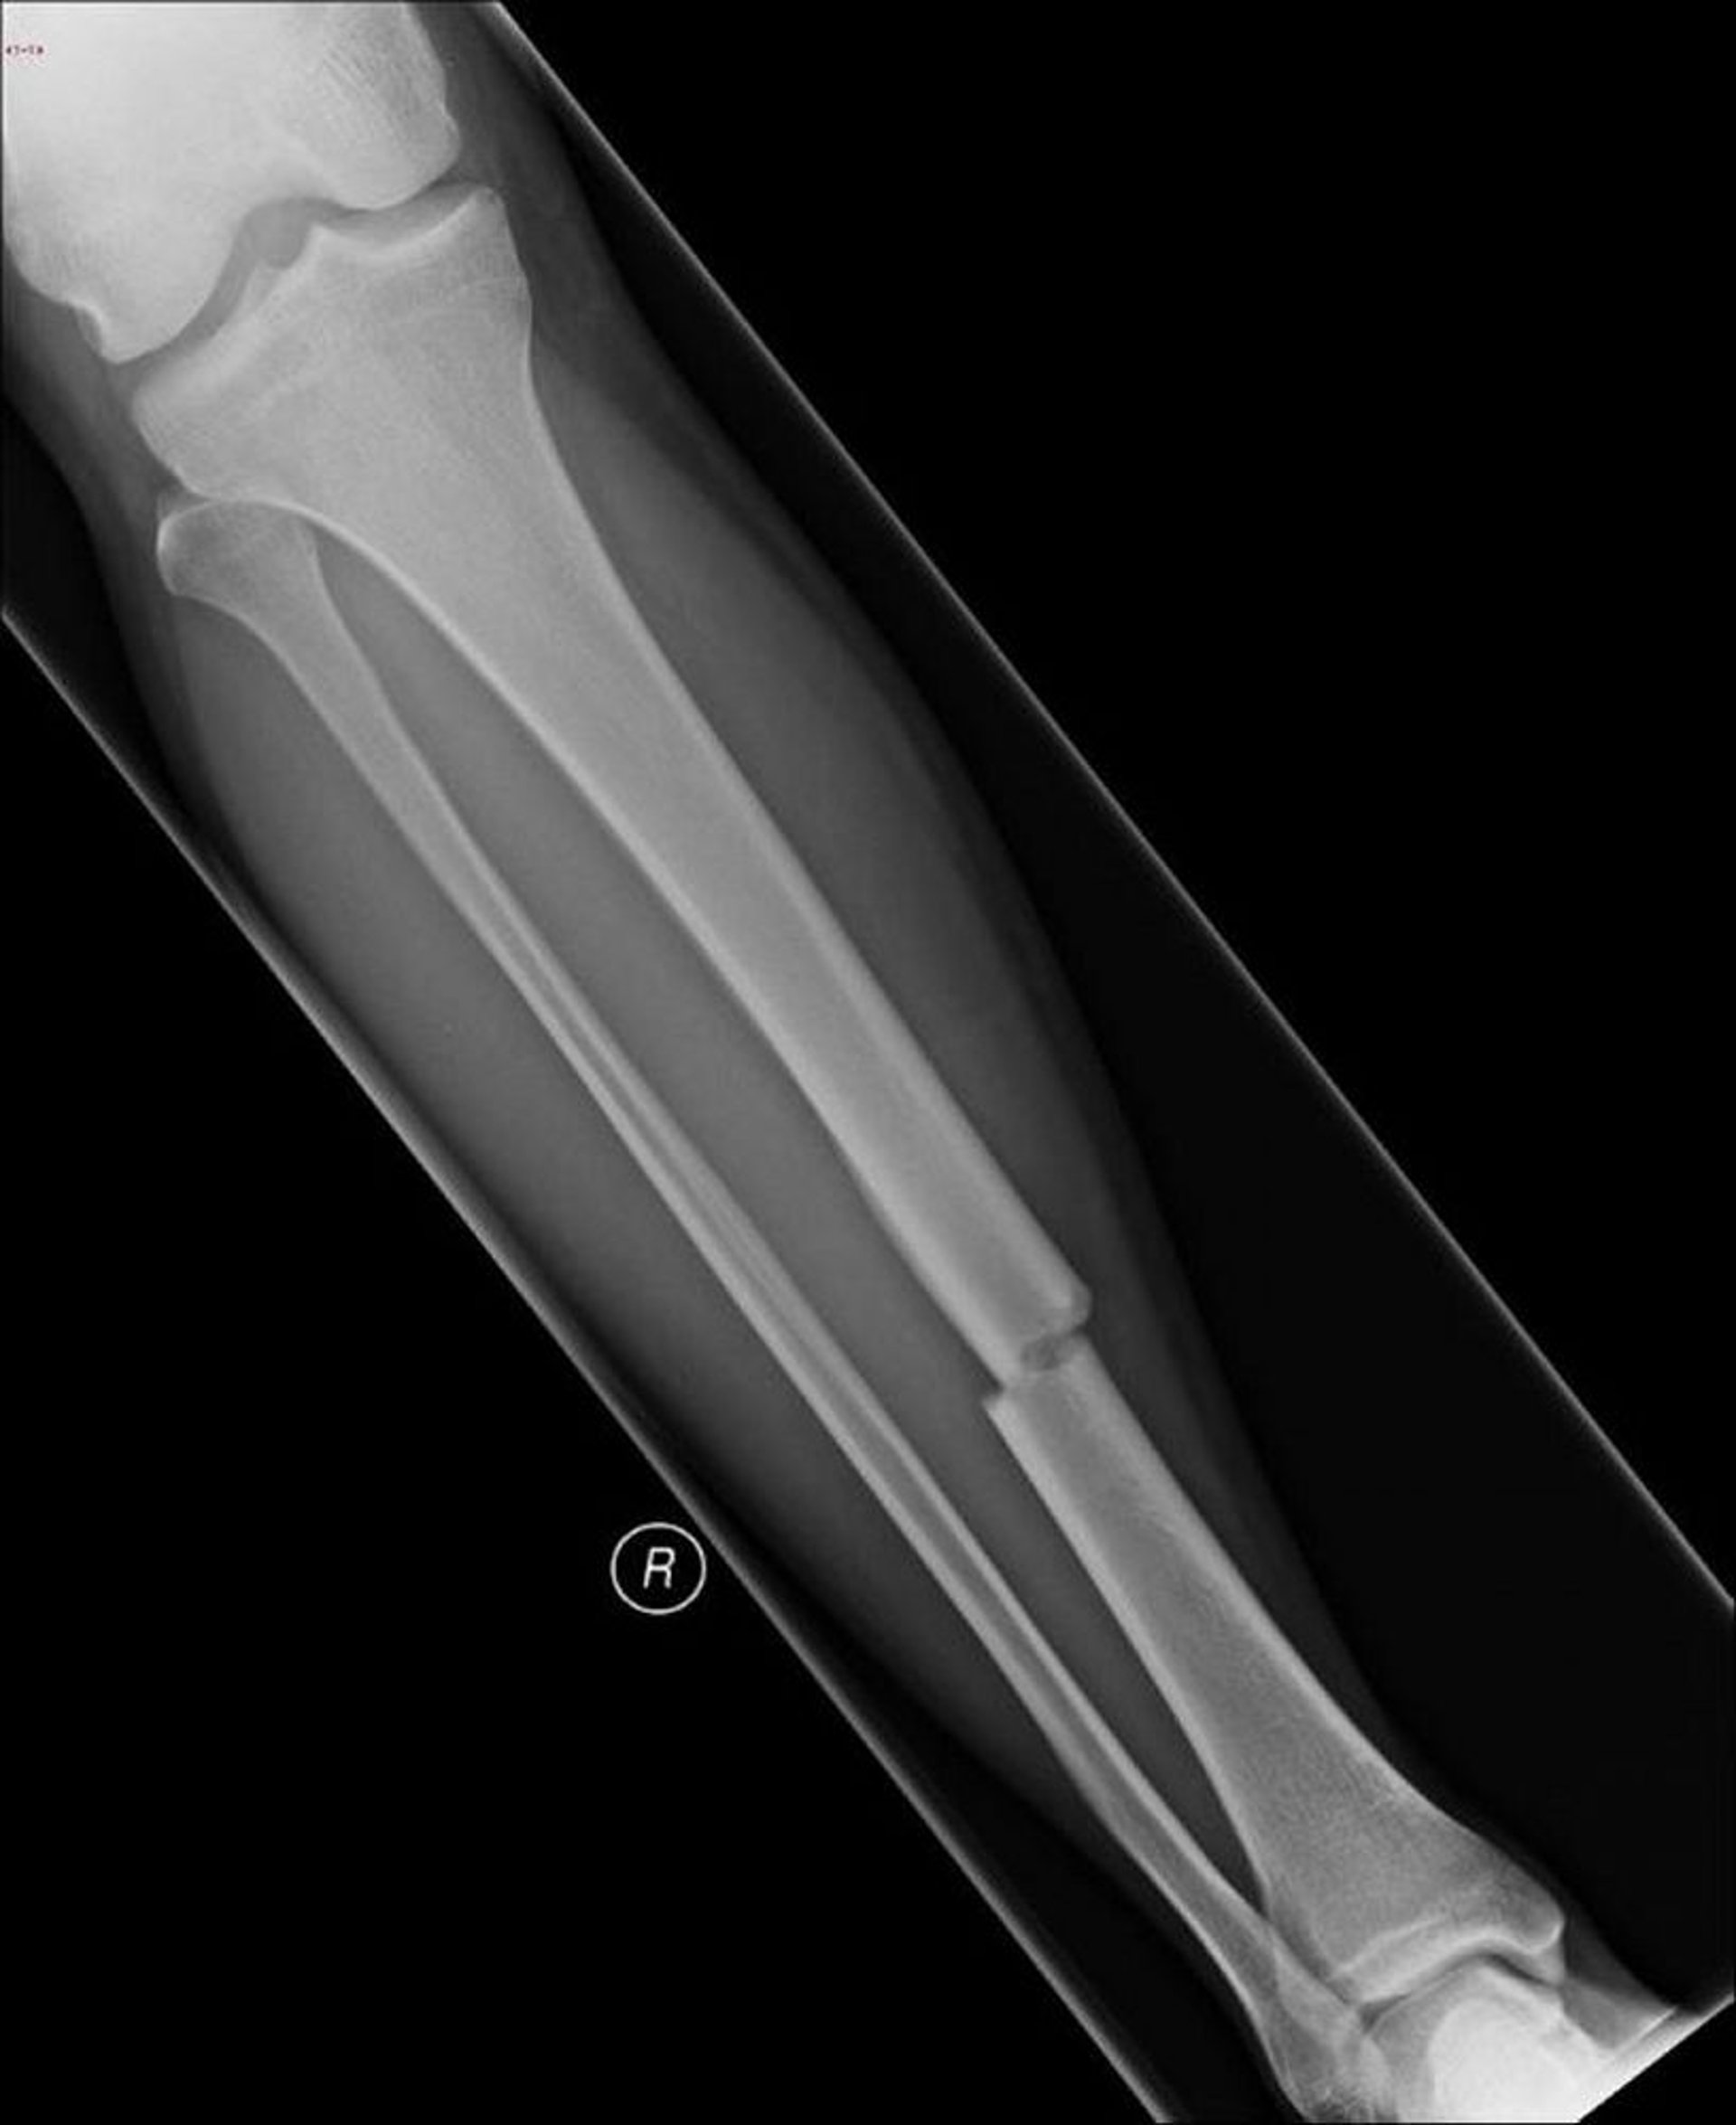

Fratura do osso da canela (tíbia)

Esta radiografia mostra uma fratura no meio do osso da canela (tíbia).

Imagem cedida por cortesia de Dr.ª Danielle Campagne.